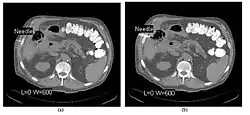

- CT Fluoroscopy (CTF) has also been referred to as Continuous CT or Real-Time CT since it involves generating tomographic images at sufficiently high frame rates to allow guidance of needle placement in small or deep-seated lesions. Applications can include biopsy of thoracic lesions, biopsy/drainage of pelvic lesions, vertebroplasty and drainage/aspiration of intracranial haematomas. The advantages of CTF include increased target accuracy and reduced procedure times[45].

- The value of N is typically 30o, 45o or 60o, with frame rates of 12, 8 and 6 frames per second, respectively. In the case of 60o updates and 6 frames per second, the delay between each image is 0.17 seconds. A Last-Image-Hold (LIH) technique can be used while the image is being updated with the resulting time lag being considered by the interventionist in terms of biopsy technique. Example images are shown in Figure 7.15.11. The display of three adjacent slices of thickness 5 mm with MDCT scanning can be used to improve visual feedback to the interventionist as the needle progresses. In addition, multi-planar reconstructions (MPR) and volume rendered 3D images can be used to enhance fine control.